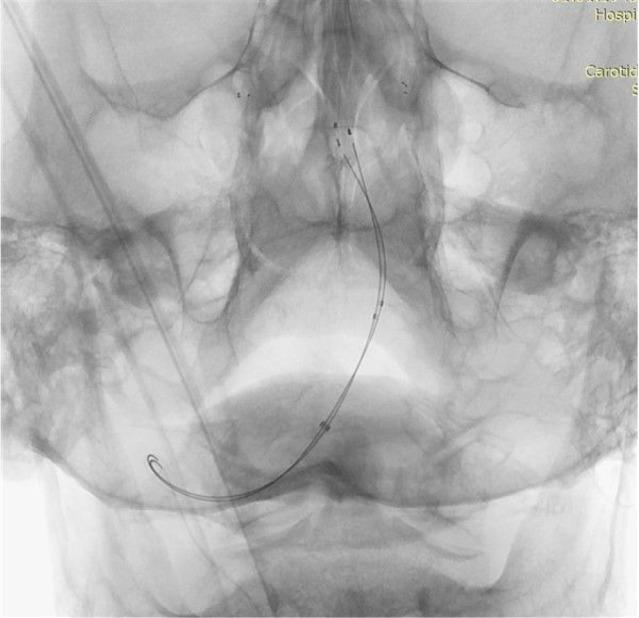

A 71-year-old man with acute basilar artery occlusion was referred for endovascular treatment 6 hours after the onset of stroke with a Glasgow Coma Score of 3 and National Institutes of Health Stroke Scale of 27. A cerebral arteriogram revealed occlusion of the left vertebral artery proximally and thromboembolic occlusion of the basilar tip. Direct aspiration and mechanical thrombectomy with various stent retrievers failed to reconstitute arterial flow in the basilar artery. Thrombolysis in cerebral infarction 2b recanalization was achieved only after placement of double Catch Mini stent retrievers through 2 microcatheters, on both side branches of the basilar bifurcation in a kissing fashion and retrieving them simultaneously. It was possible to perform this maneuver through a single distal access catheter without any complications. On follow-up the patient awakened and was able to follow commands on his right side. To our knowledge, dual mechanical thrombectomy with stent retrievers has not been reported in the posterior circulation previously. This technique may be useful in retrieving thrombi located at major intracranial bifurcations of the posterior circulation which do not recanalize with standard mechanical thrombectomy procedures. Although bilateral access to the basilar artery through both vertebral arteries is an advantage in posterior circulation for this technique, dual mechanical thrombectomy can also be performed through a unilateral access.

一名71岁急性基底动脉闭塞男性患者,在卒中发作6小时后被转诊接受血管内治疗,格拉斯哥昏迷评分为3分,美国国立卫生研究院卒中量表评分为27分。脑血管造影显示左椎动脉近端闭塞,基底动脉尖部血栓栓塞性闭塞。使用各种取栓支架进行直接抽吸和机械取栓均未能恢复基底动脉血流。仅在通过2根微导管在基底动脉分叉的两侧分支以对吻方式放置双Catch Mini取栓支架并同时取出后,才实现了脑梗死2b级溶栓再通。通过单个远端通路导管即可完成此操作,且无任何并发症。随访时患者苏醒,右侧能够听从指令。据我们所知,此前后循环中尚未报道过使用取栓支架进行双重机械取栓。该技术可能有助于取出位于后循环主要颅内分叉处、采用标准机械取栓程序无法再通的血栓。尽管通过双侧椎动脉对基底动脉进行双侧入路在该技术的后循环中是一个优势,但双重机械取栓也可通过单侧入路进行。